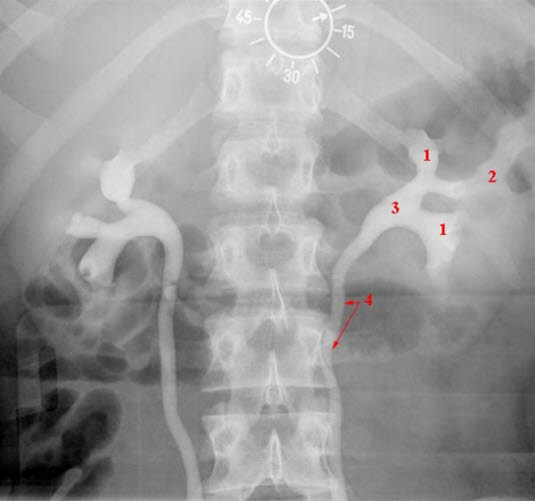

Normal oppladning i nyreparenkym og utskillelse til velfylt samlesystem ca. 10 minutter etter kontrast

- Calyces

- Nyreparenkym

- Nyrebekken

- Urinleder